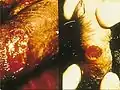

Lésions du pénis

De petits nodules, indolores apparaissent environ 10 à 40 jours après le contact avec la bactérie. Plus tard, les nodules éclatent, aboutissant à la création des lésions tissulaires ouvertes et suintantes. L'infection se propage, mutilant les tissus infectés. En l’absence de traitement l'infection continue à détruire les tissus. Les lésions apparaissent dans les régions de contact sexuel généralement sur le pénis, les lèvres vulvaires, ou l’anus. Plus rarement, la paroi du vagin ou du col de l'utérus peuvent être le siège de lésions. Un cas dont l'évolution a nécessité l'amputation partielle du pénis a été décrit chez un patient indien infecté par le VIH-2 [9].